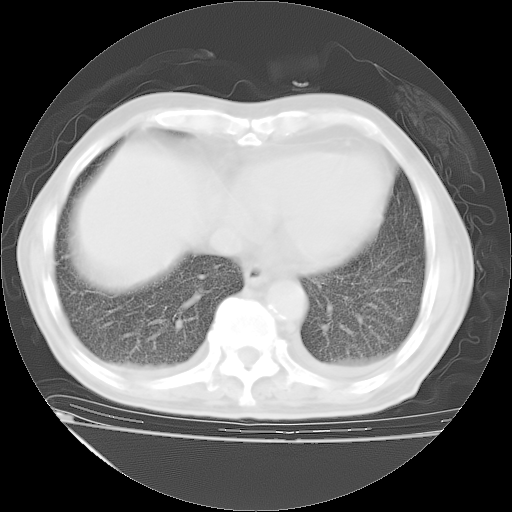

甲强龙80mg/日+抗结核治疗(异烟肼+利福霉素+乙胺丁醇)10天。复查肺部CT。

治疗10天肺部CT

补充下:5月9日胸部CT:似乎已见双下肺胸腔积液了,鉴于目前有下肢水肿,肝功示:白蛋白低,应注意多浆膜腔积液(漏出液可能大?),需注意!